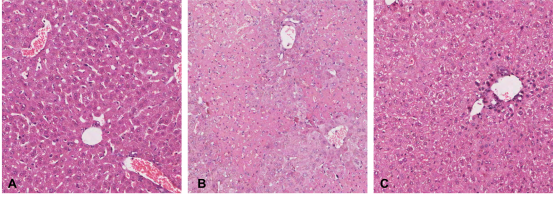

邓志华课题组查阅大量文献资料,发现肝星状细胞(HSC)在肝纤维化中发挥关键作用,此外近年研究还发现HSC具有免疫细胞特征,直接参与肝脏的免疫调控,但由于HSC是肝脏的非实质细胞,数量极少,分离小鼠原代HSC非常困难,限制了其研究进展。课题组经过不断摸索研究,运用OptiPrep分离液结合原位手工灌注法分离到BALB/c小鼠高纯度高得率的原代HSC,倒置荧光显微镜下观察:新分离的HSC呈圆形,具有丰富的脂滴,在328nm波长的紫外光激发下自发蓝绿色荧光,逐渐从圆形变为梭形或星形,培养7d后,伸出细长的伪足。原代HSC油红O染色阳性,胞浆中的脂滴呈红色,细胞核呈蓝色,传2代后免疫细胞化学染色HSC完全表达α-SMA和Desmin,自发活化。课题组进一步将BALB/c来源的HSC与C57BL/6小鼠脾脏来源的Treg细胞共培养,观察HSC对Treg的诱导作用,异体活化的HSC可在体外呈剂量依赖性、通过细胞-细胞直接接触方式诱导Treg增殖,扩增的Treg可有效表达FoxP3,在体外可有效抑制Teff细胞增殖。为进一步证实扩增的Treg的免疫调节活性,将扩增的Treg通过尾静脉注射到ConA诱导的AIH小鼠体内,观察其对AIH小鼠受损肝脏的影响,发现扩增的Treg可调节AIH小鼠脾脏Treg/Th17比例失衡,肝脏炎症和肝细胞坏死明显减轻[图2],血清ALT、AST水平IL-6、TNFα、IFN-γ水平降低,发挥了良好的治疗作用。该课题为寻找替代糖皮质激素/硫唑嘌呤治疗AIH的免疫细胞疗法提供了可靠的实验研究结果。

图2过继转移体外扩增的Treg细胞后AIH模型小鼠肝脏病理变化(A:正常肝脏B:AIH模型肝脏C:过继转移Treg后肝脏)